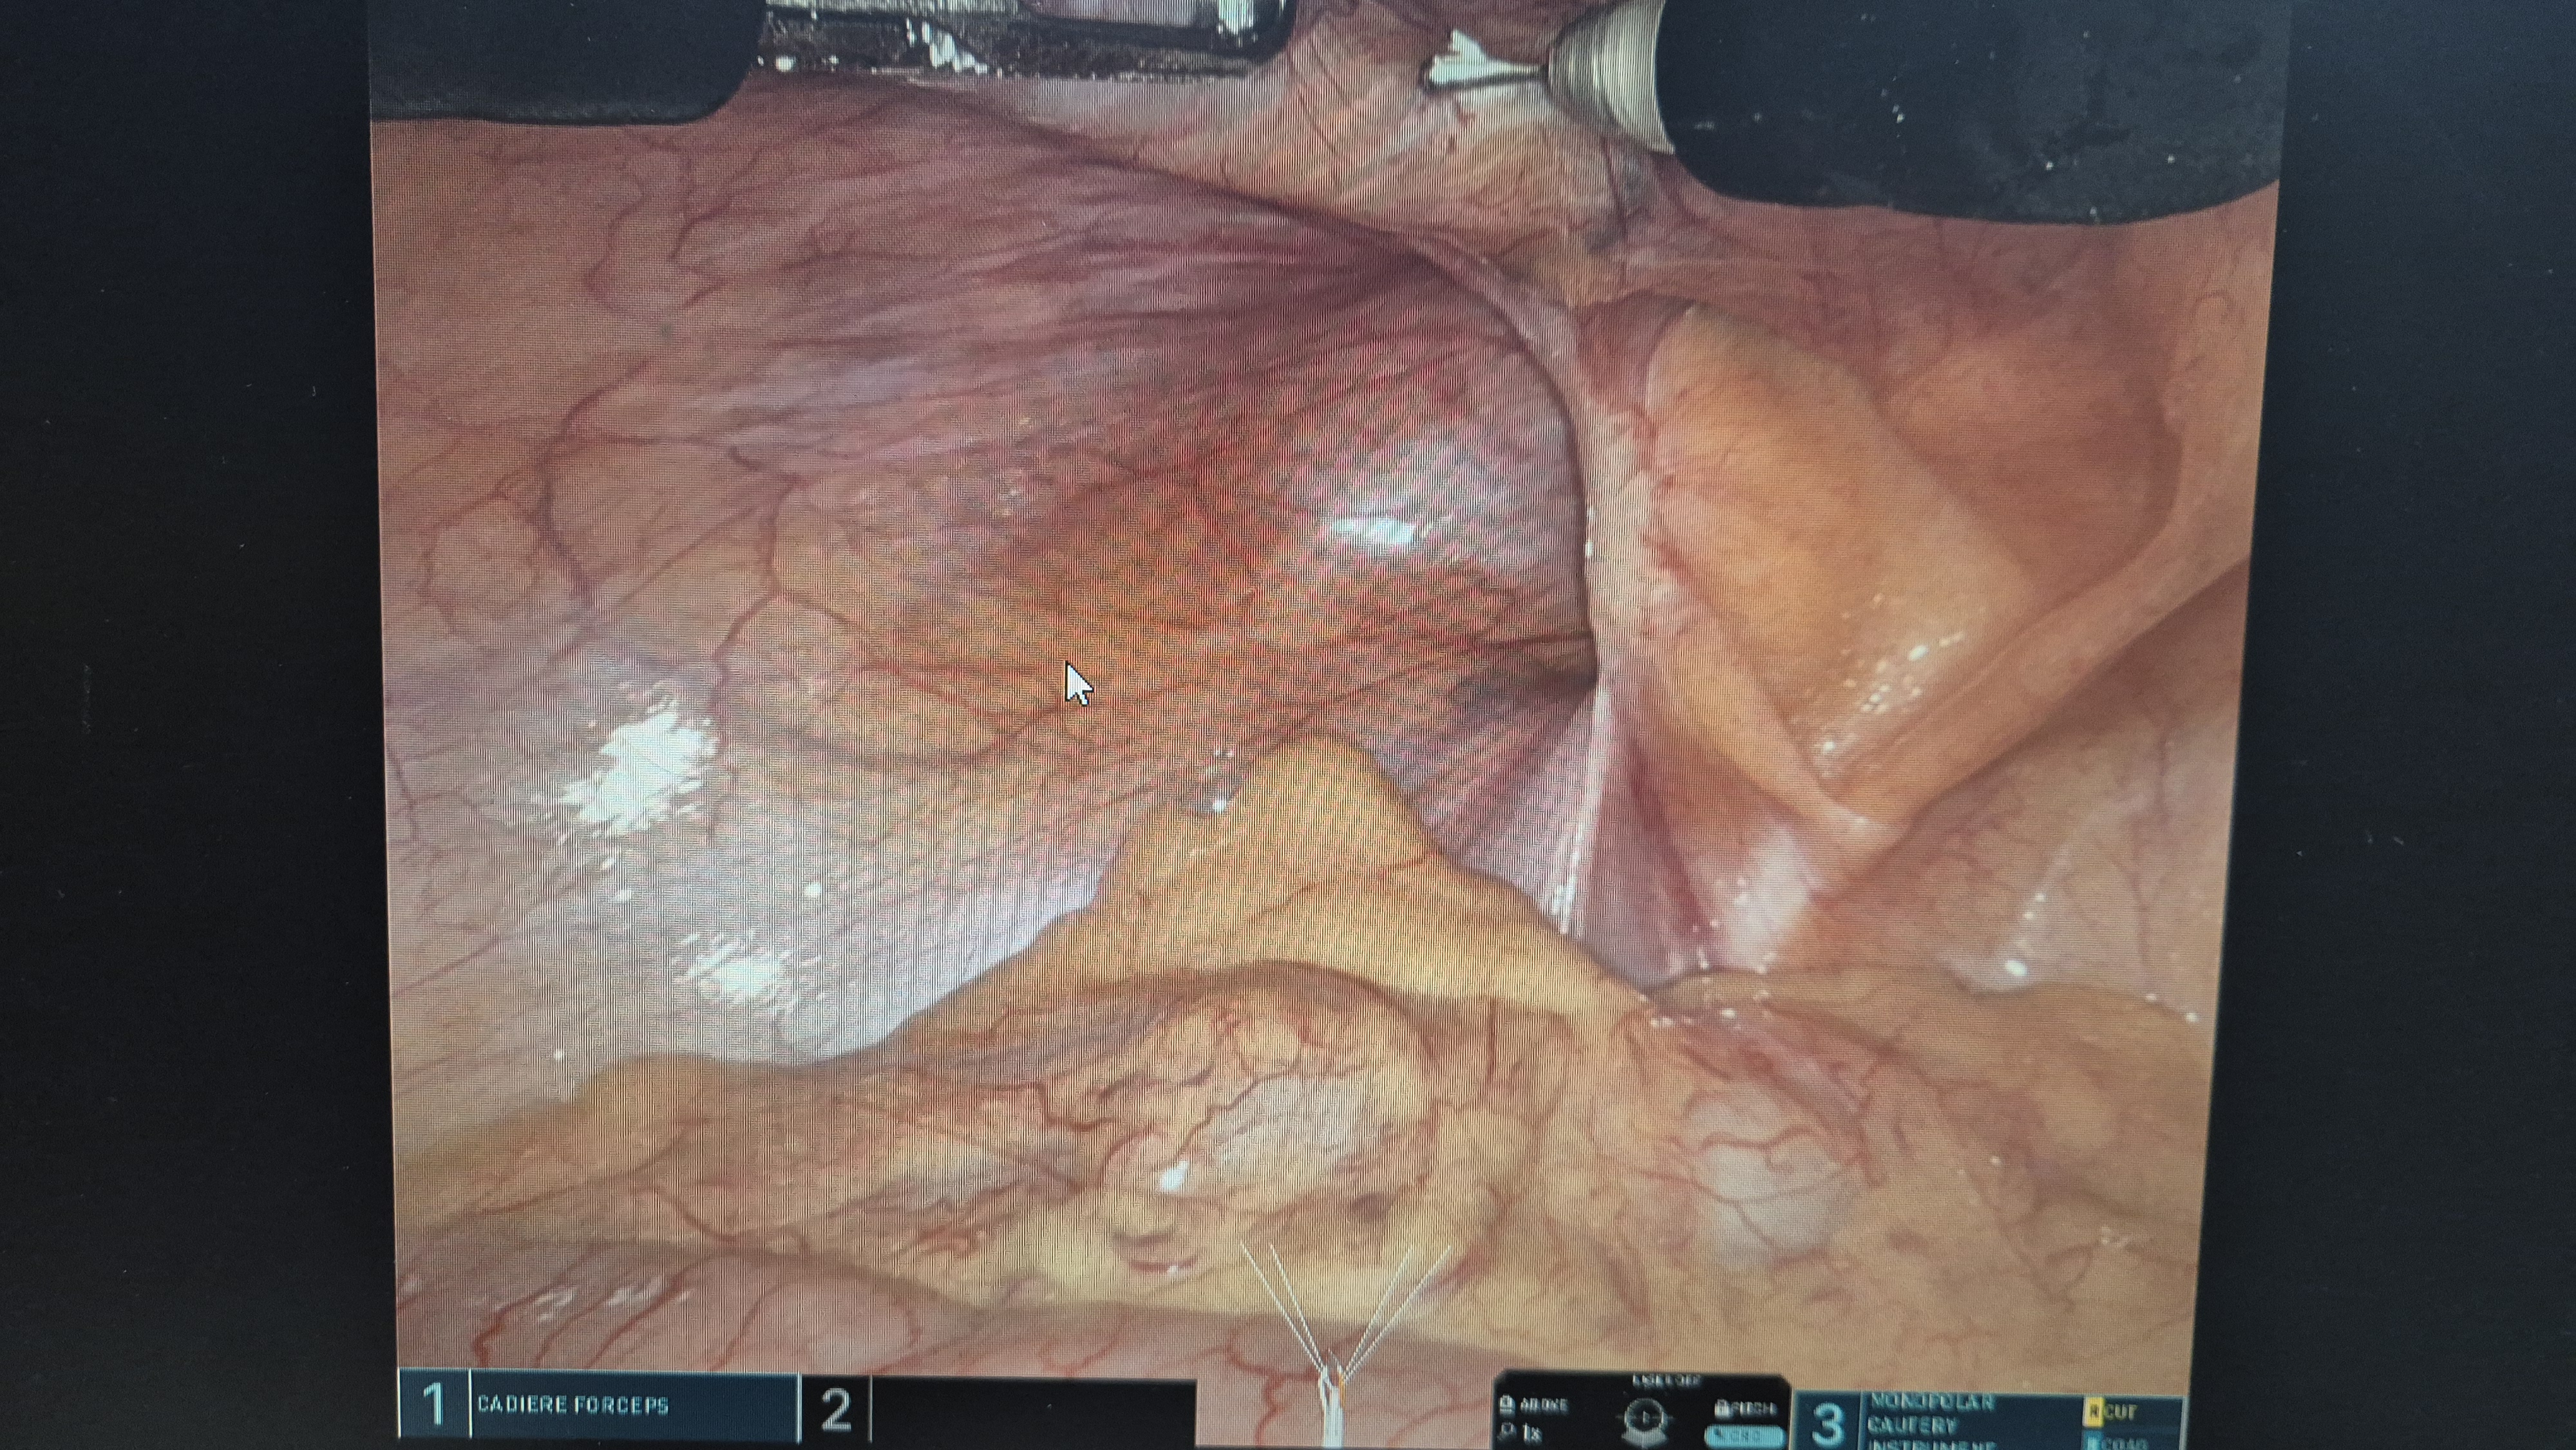

방금 다빈치sp 로봇 탈장교정술을 시행했습니다.

다빈치 sp. 탈장 교정술은 배꼽에 단 하나의 구멍을 통하여 양측 모두 수술합니다.

좌측 간접 서혜부 탈장.

복막 열고.

메쉬로 고정.

복막 봉합.

우측 직접 서혜부 탈장.